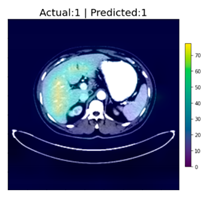

After reaching an accuracy of 95.89%, the training was stopped, and the Grad-CAM method was applied for each of the test images, including those that were falsely classified. The following figure, Figure 6, shows some of the CT images with their associated heat-maps overlaid. In the legends of the figures, “Actual” shows the label for DeepLesion, and “Predicted” shows the output of the CNN classifier.

Figure 6.

CT images with Grad-CAM-generated heat-maps overlaid.